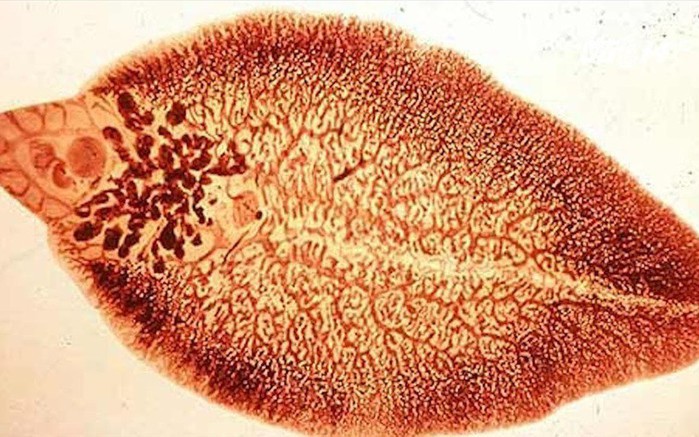

Đau dạ dày, ngoài việc dùng thuốc điều trị thì cách ăn uống, sinh hoạt hằng ngày cùng chế độ ăn cũng quyết định nhiều cho việc điều trị thành công. Ảnh minh hoạ